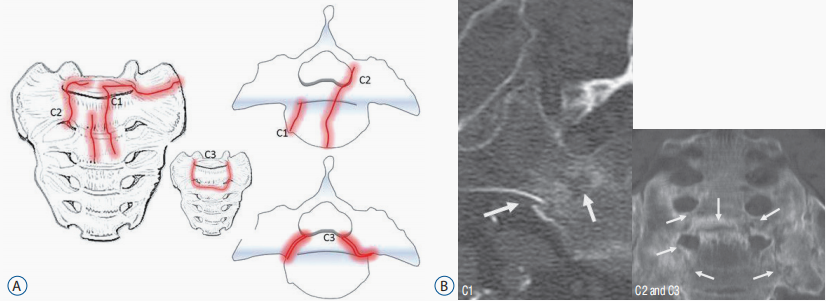

骶骨 C 型骨折

注:C 型-骶骨中央骨折 C1-骨折线从前缘向背侧或骶髂关节移动 C2-骨折线累及单侧骶孔或骶管 C3-横向骨折伴双侧矢状骨折(不稳定)